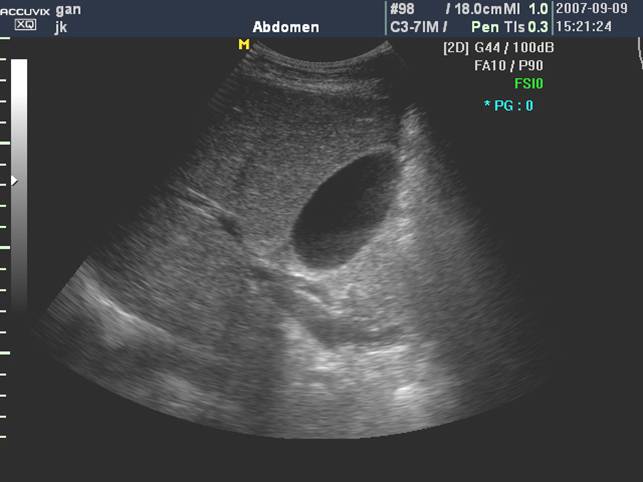

(二)门静脉

门静脉主干是由肠系膜上静脉和脾静脉在胰颈背侧汇合而成,居于胆总管和肝动脉之后。

门静脉从第一肝门开始,分左右两大支。左支沿横沟向左侧横行行走,名左支横段,待抵达左内、外叶交界处,折向足端走,与横段垂直,形成独特的“C”形结构称矢状段, 末端稍膨大称囊部,与肝圆韧带相连,后者为脐静脉闭锁后的残迹。

门静脉左干横部、矢状部及左内叶支和左外叶上、下段支的空间投影图像呈“工”字形:

门静脉右支较短,约1.5cm左右,向右水平走行分成右前支和右后支,前支和后支分别再分成上段支和下段支:

门静脉右干及分支,当探头沿着门静脉主干右上方移动可显示右干,其远端“Y”型分叉:

门静脉主干及右支长轴和胆囊长轴呈空间"垂直",立体投影空间排列呈"飞鸟样":